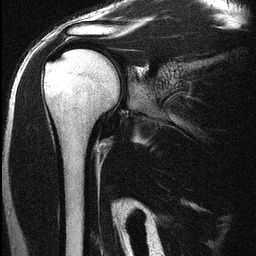

Un cuadro de diálogo aparecerá, (imagen 1) pide número de muestra de puntos, altura y cómo crear la superficie. Puntos de muestra son exactamente lo que significa la más puntos de muestra, la mas detallada será el modelo. Altura será otra vez, Cuánto mide el objeto. La diferencia entre "puntos en los lugares de muestra" y "interpolación de superficie a través de las muestras" es la cantidad de detalles que tienes en tu heightfield. En la imagen que posteé (imagen 2), hice algunos ejemplos, utilizando una de mis imágenes de resonancia magnética. Como se puede ver, bajar resultados de puntos de resolución y control en una superficie muy baja y suave, mientras que una alta resolución y una superficie resultados interpolados en una superficie que es extremadamente detallada e irregulares. Para efectos de contorno de topo, me parece que el método de punto de control es ideal.